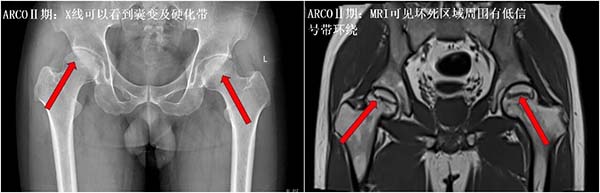

①坏死分期:

不同分期的股骨头坏死,恢复效果和治疗方向天差地别,大家可以对照参考:

ARCOⅠ、Ⅱ期:股骨头还没有塌陷,关节形态完好,此时若及时发现、规范干预,保髋成功率非常高,大多数人可以避免或推迟关节置换,预后最好;

ARCO Ⅲ期:股骨头已经出现塌陷,关节功能开始受损,保髋难度明显增加,预后也会变差,部分人可能需要接受更复杂的保髋手术;